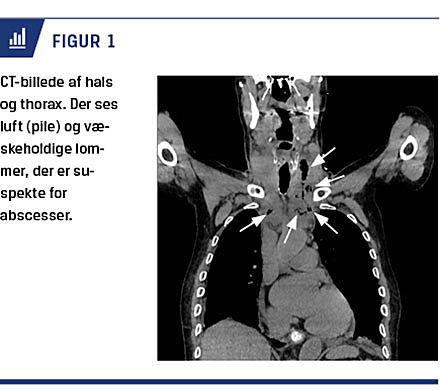

Ved næste besøg havde han feber, og smerterne i venstre side af halsen var uændrede. Han blev derfor akut indlagt. Biokemien viste bakteriel infektion med et trecifret C-reaktivt protein-niveau, og han blev sat i peroral behandling med penicillin. Der blev på indlæggelsesdagen udført direkte laryngoskopi og fleksibel øsofagoskopi i generel anæstesi (GA), hvor man fandt intakte slimhinder og intet fremmedlegeme. Man fandt ligeledes ingen tegn til infektion i mund eller svælg. Infektionstallene var fortsat stigende, og behandlingen blev skiftet fra penicillin til intravenøst givet cefuroxim og metronidazol. En CT af hals og thorax med kontrast viste i venstre side af halsen et subkutant emfysem, der strakte sig fra glandula thyroidea ned til mediastinum. Kontrastvæsken passerede frit til ventriklen, så der var ingen perforation. Pga. tiltagende febrilia, stigende infektionsparametre og rødme på halsen og brystet blev cefuroxim erstattet med piperacillin/tazobactam. CT blev gentaget og viste fortsat emfysem og væskeholdige lommer, der formentlig udgik fra venstre forside af øsofagus ud for glandula thyroidea (Figur 1). Der blev derfor planlagt kirurgisk intervention i GA. Der blev incideret horisontalt midt imellem cricoidet og jugulum. Abceslommer blev opsøgt på begge sider af halsen og retrosternalt. Ved tryk på halsen og brystet fremkom der massive mængder af pus. Der blev lagt nøgendræn ned mod klaviklen bilateralt, og retrosternalt blev der pakket med meche. De efterfølgende dage blev der kvitteret store mængder pus fra drænene. Der blev dagligt udført oprensning og meche-skift i GA. En CT af hals og thorax seks dage efter det første kirurgiske indgreb viste væsentlig regression af abscesserne. Der var dog tilkommet bilateral pleuravæske, og der blev udtømt en liter klar, strågul væske. Dyrkning var uden vækst. Der blev ligeledes podet fra pus i flere omgange, uden at der blev fundet vækst af patogene bakterier. Ni dage efter incidering blev drænene fjernet og antibiotika seponeret. Patienten blev udskrevet og fulgt ambulant i yderligere en måned til såret på halsen var helt lukket.